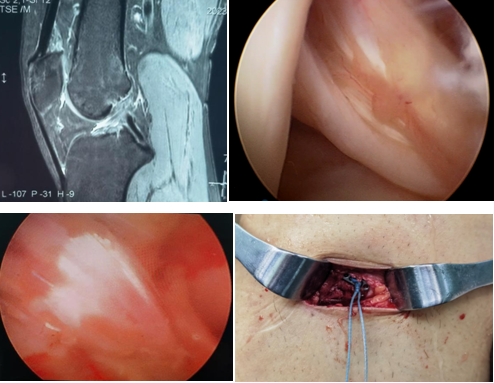

近日,一名31岁男性因打篮球扭伤致“右膝关节疼痛伴行走不稳半年”入院,术前诊断:前交叉韧带部分断裂。考虑患者年轻且有较高的运动恢复需求,在骨科病院刘时璋主任医师的指导下,由冯敏副主任医师主刀完成六合彩网站

首例关节镜辅助下前交叉韧带损伤“保残+全内”重建术。患者第二日即下地活动,第三天顺利出院。

ACL的保残重建具有有效促进ACL移植物血管再生,促进损伤ACL本体感觉的恢复,以及防止ACL术后隧道扩大等多种技术优势。而ACL的全内重建技术是国际上新近发展出现的另一项新技术,相比传统方法,它仅需获取自身单根肌腱,而且所需长度远小于传统重建方法。另外,此技术保留了更多的骨皮质及骨膜,术后疼痛更少,腱骨愈合更佳,同时有效降低了术后感染风险,避免了传统方式界面螺钉对肌腱的切割作用。